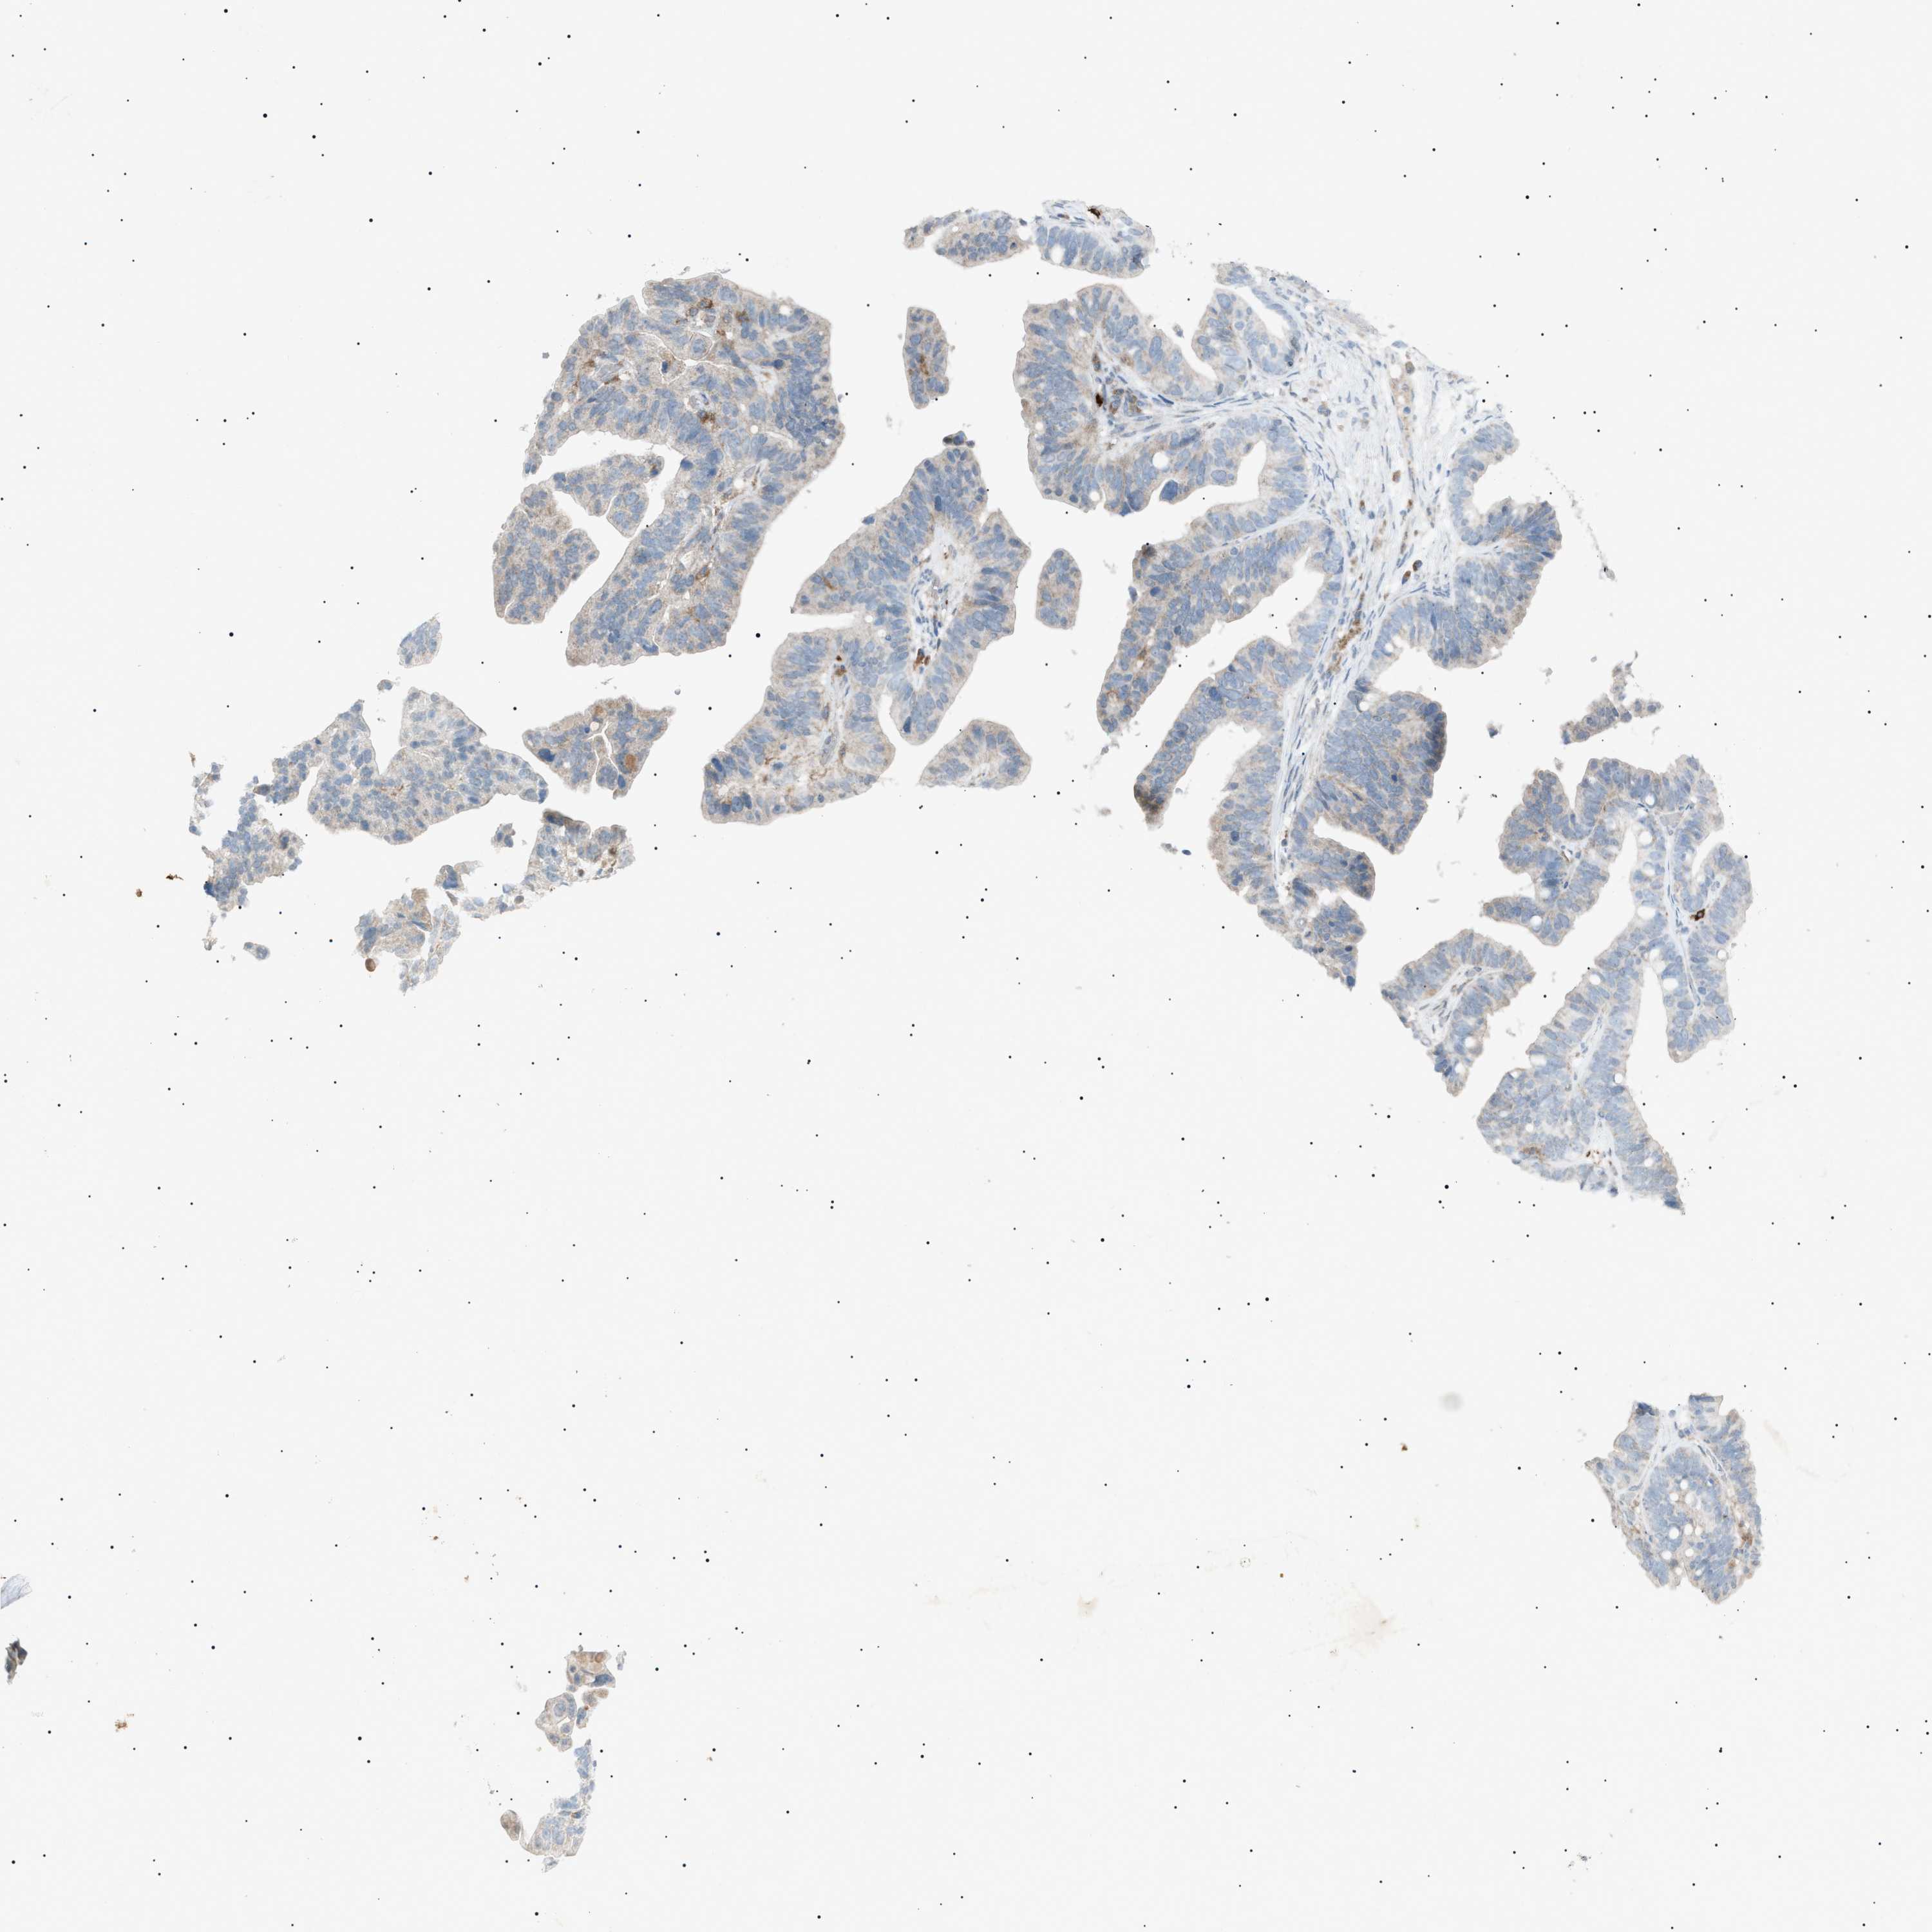

OVARIAN CANCER - Protein expressioni

A mouse-over function shows sample information and annotation data. Click on an image to view it in a full screen mode. Samples can be filtered based on level of antibody staining by selecting one or several of the following categories: high, medium, low and not detected. The assay and annotation is described here.

Note that samples used for immunohistochemistry by the Human Protein Atlas do not correspond to samples in the TCGA dataset.

Antibody stainingi

Antibody staining in the annotated cell types in the current human tissue is reported as not detected, low, medium, or high, based on conventional immunohistochemistry profiling in selected tissues. This score is based on the combination of the staining intensity and fraction of stained cells.

Each image is clickable and will lead to virtual microscopy that enables deeper exploration of all samples and also displays staining intensity scores, fraction scores and subcellular localization as well as patient and tissue information for each sample.

Antibody HPA001198

Antibody HPA002028

Antibody CAB016689

Antibody CAB080300

Cystadenocarcinoma, mucinous, NOS

Carcinoma, endometroid

Cystadenocarcinoma, serous, NOS

Carcinoma, NOS